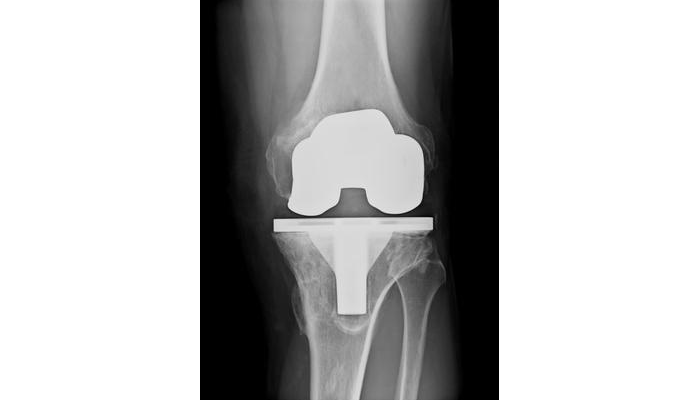

Case Study: Total Knee Replacement Patient with Wound Dehiscence Due to Lymphedema

Managing Wound Dehiscence with Chronic Lymphedema

Patient L entered our facility from an acute care hospital. She had already failed discharge home and arrived with a diagnosis of incision and drainage of her infected knee replacement with heavy wound drainage. She required more than one dressing change per day (even with wicking ultra-absorbent dressings). Her topical dressing was changed to a post-op negative pressure wound therapy (NPWT) dressing at 125mmHg continuous. The dressing was applied in a partially flexed position to allow range of motion (ROM) exercises. Output required changing the 300ml canister BID. Her comorbid diagnosis of chronic lymphedema was obviously slowing the healing of her surgical incision such that even the NPWT pump could not keep up with it. Her physicians cleared her for Manual Lymphatic Drainage (MLD) and multilayer compression bandaging when an ABI showed adequate arterial circulation.